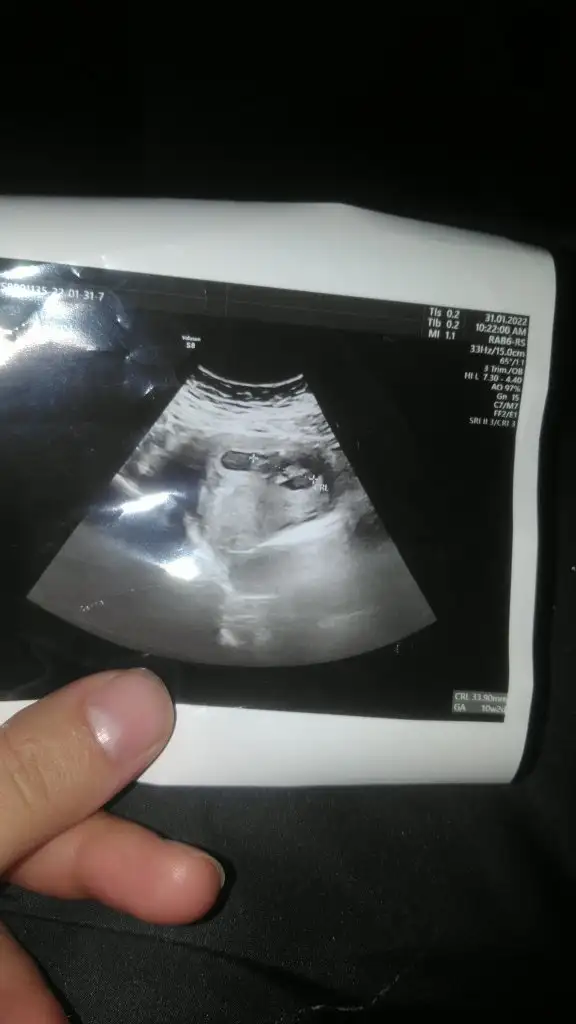

Merhaba merak ettim cinsiyet ne çıktı acaba :)Arkadaslar cok merak ediyorum yaaaa anlyan varsa yorumlar mo acabaaa

Benim de yukarı doğru uzun bakalım ne olacak cinsiyetiMerhaba benimde uzundu yukarıya doğru ve erkek oldu :)

Var mi resmi canimBenim de yukarı doğru uzun bakalım ne olacak cinsiyeti

Hamile kaldığım ay 30 haziran veya temmuz başıBenim ultrasonumuda yorumlarmısınız rica etsem